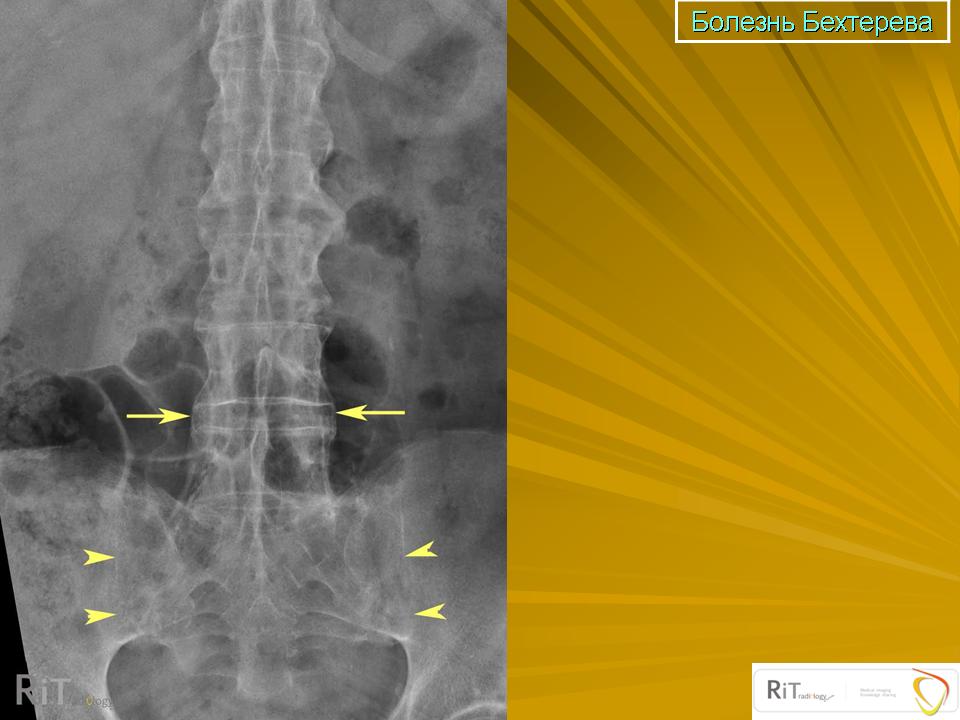

АНКИЛОЗИРУЮЩИИ СПОНДИЛОАРТРИТ (Болезнь Бехтерева)

Рентгенологические изменения обычно начинают выявляться в крестцово-подвздошном сочленении. В течении сакроилеита выделяют 4 стадии.

1. Нечеткость, расплывчатость контуров крестца и подвздошной кости. Субхондральный склероз.

2. Образование узур с развитием субхондрального склероза в области сочленения, кажущееся расширение щели, неровные ее контуры.

3. Резкое сужение щели, субхондральный склероз.

4. Полный анкилоз.

Сакроилеит I—II стадии развивается, по данным В. М. Чепой (1978), в течение первых 5 лет болезни. У 10% больных в течение первых 3-х лет болезни может отмечаться односторонний процесс, а затем он принимает двусторонний характер.

Важным симптомом является анкилоз в межпозвонковых суставах (выявляется на косых рентгенограммах). При этом появляется неровность, нечеткость контуров замыкательных пластинок, субхондральный склероз в области суставных поверхностей отростков, сужение, а затем и анкилоз суставов. Часто приходится наблюдать синдесмофиты — обызвествление наружных отделов фиброзного кольца. Фиброзный мостик находится в периферических отделах фиброзного кольца и вне связок. Чаще синдесмофиты появляются на уровне LV — SI,

Тh XII —LI.

Таким образом на рентгенограммах выявляются следующие изменения:

— описанные изменения в крестцово-подвздошном сочленении,

— образование синдесмофитов,

— симптомы обызвествленния передних продольных связок в виде остеофитов в области боковых отделов тел позвонков,

— непрерывная линейная тень в области остистых отростков за счет обызвествления межостистых и надостистых связок,

— плотные, не совсем четкие линейные тени на уровне основания дужек — за счет обызвествления желтых связок (связывающих суставные отростки).